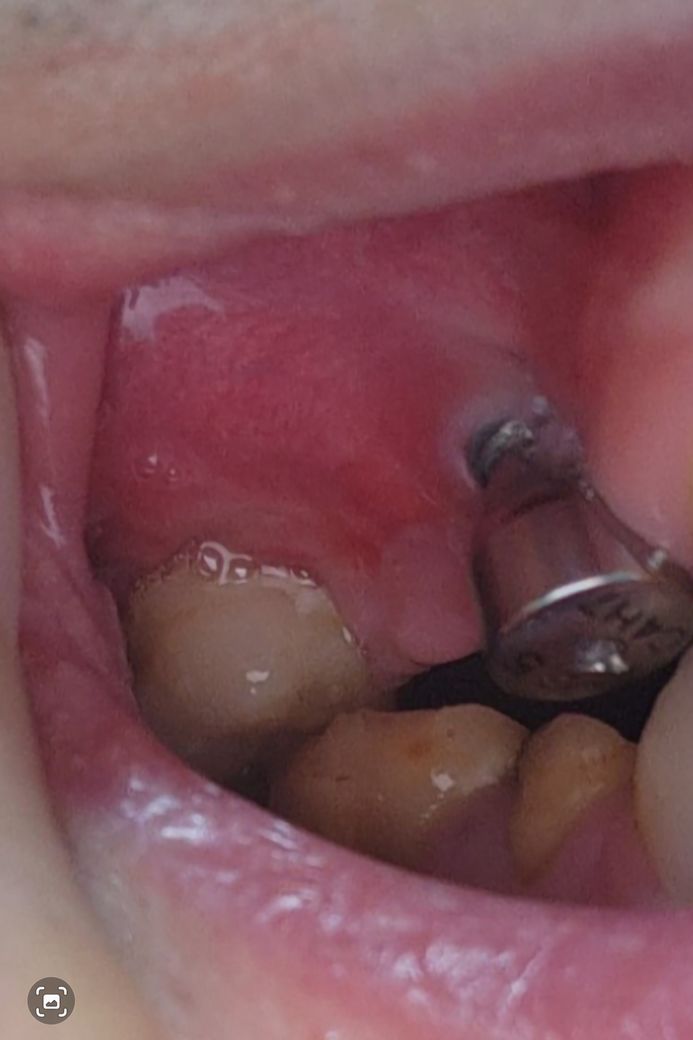

잇몸 빨간 상처 임플란트 염증 일까요~?

8월8일부터 잇몸이 아팠습니다.

처음에는 구내염인가 싶어 지켜봤는데 잇몸에 구멍과 더불어 8월14일부터 양치질을 쎄게 한건지 빨간게 생겨서 이렇게 여쭈어봅니다.

임플란트식립 부위 잇몸에 염증이 생긴것으로 보입니다. 원인은 치석이 쌓여 잇몸을 자극하였을 가능성도 있으며, 방치시에 잇몸염증이 악화되어 임플란트 식립에도 문제를 주기에 빠른 시일내에 치과 치료가 필요로 됩니다.

임플란트 심으신데 염증이 생겨서 잇몸이 많이 내려간거 같은데 치과에 가셔서 검진을 받아보시는게 좋을것같습니다.

잇몸에는 붉은색을 띠는 부분이 있습니다.

임플란트 주변에도 경미한 염증이 보이는듯해 보여요.

사진으로만 판단하기에는 염증의 여부를 정확하게 알기 어렵습니다.